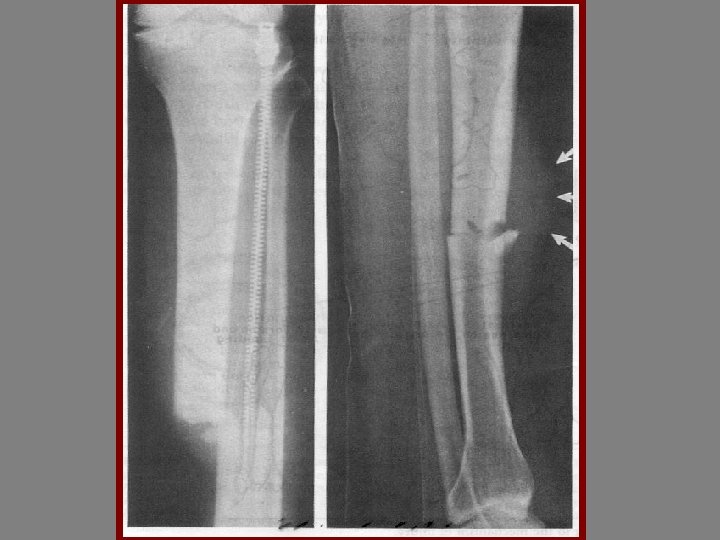

BONE HEALING 1 -INFLAMATORY PHASE 5%-10% 2 -REPARATIVE PHASE 40% 3 -REMDELING 70%